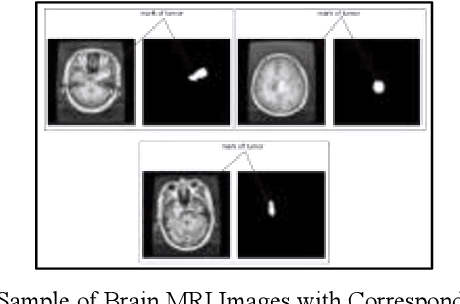

Abstract:This study systematically investigates the impact of image enhancement techniques on Convolutional Neural Network (CNN)-based Brain Tumor Segmentation, focusing on Histogram Equalization (HE), Contrast Limited Adaptive Histogram Equalization (CLAHE), and their hybrid variations. Employing the U-Net architecture on a dataset of 3064 Brain MRI images, the research delves into preprocessing steps, including resizing and enhancement, to optimize segmentation accuracy. A detailed analysis of the CNN-based U-Net architecture, training, and validation processes is provided. The comparative analysis, utilizing metrics such as Accuracy, Loss, MSE, IoU, and DSC, reveals that the hybrid approach CLAHE-HE consistently outperforms others. Results highlight its superior accuracy (0.9982, 0.9939, 0.9936 for training, testing, and validation, respectively) and robust segmentation overlap, with Jaccard values of 0.9862, 0.9847, and 0.9864, and Dice values of 0.993, 0.9923, and 0.9932 for the same phases, emphasizing its potential in neuro-oncological applications. The study concludes with a call for refinement in segmentation methodologies to further enhance diagnostic precision and treatment planning in neuro-oncology.